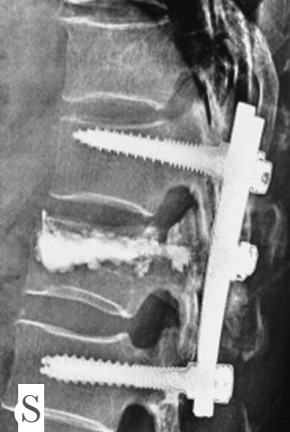

Spinal Trauma & Fracture Stabilisation

Prompt, accurate management of spinal fractures and spinal cord injuries is crucial for recovery.

Dr. Sivaraj specialises in stabilisation surgery, decompression, and rehabilitation following accidents, falls, or osteoporosis-related fractures.

Treatment goals:

Early neurological recovery

Restoration of alignment

Pain control and mobility